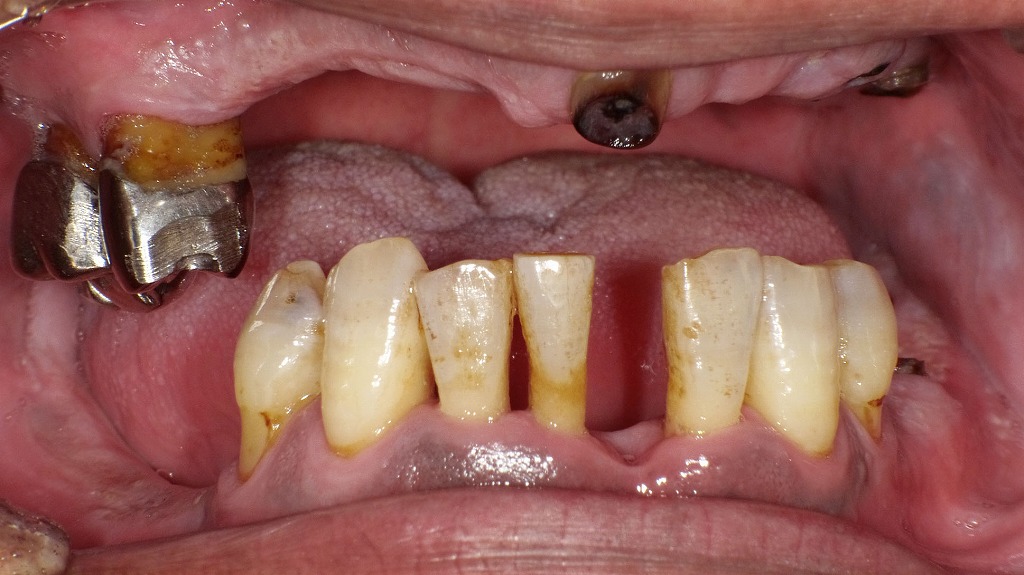

歯周病による慢性的な炎症は血糖コントロールを悪化させ、糖尿病は免疫力の低下により歯周病を進行させやすくします。歯ぐきの腫れや出血、歯の動揺が見られる場合、糖尿病の管理と歯周病治療を並行して行うことが重要です。口腔ケアは、全身の健康管理の一部として欠かせません。

🧬 なぜ糖尿病の人は歯周病になりやすいのか?

糖尿病の人は、高血糖の状態が続くことで免疫力が低下し、細菌に対する防御力が弱くなります。また、血管障害により歯茎の血流が悪化し、炎症を抑える力も低下。その結果、歯周病菌に感染しやすく、歯ぐきの腫れや出血が起こりやすくなります。

さらに、唾液の分泌量が減少することで口腔内が乾燥し、細菌が繁殖しやすい環境が整ってしまうのも大きな要因です。